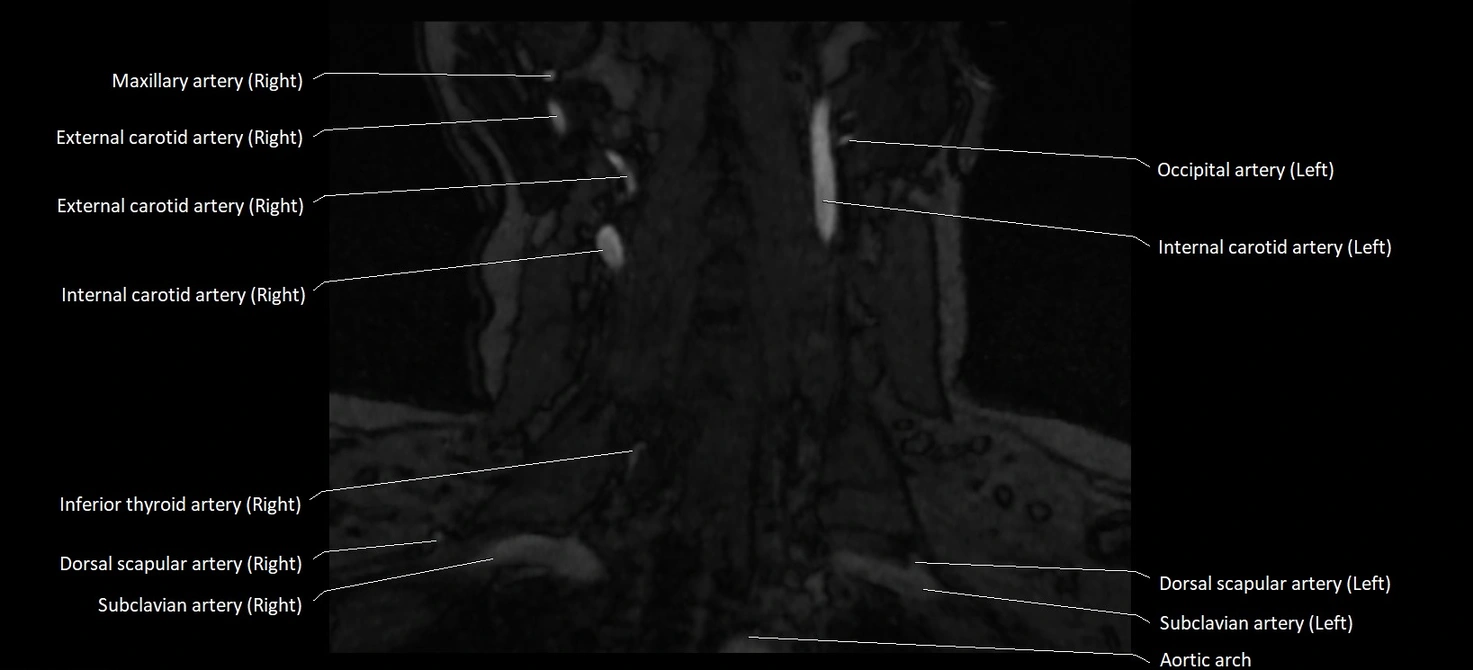

CT image

image